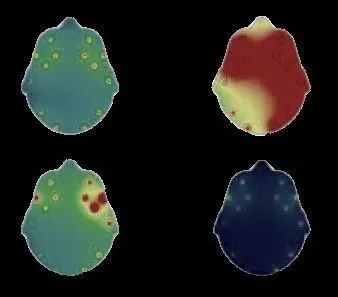

今天我们的任务是从包含患者大脑活动快照的图像中提取所需的片段。之后可以将该提取的过程应用于其他程序中,例如诊断健康与否的机器学习模型。

因此,让我们从查看输入图像开始。这是由神经科学领域的医疗仪器生成的典型报告,该仪器使用传感器检测来自患者大脑的信号并将其显示为彩色地图。通常,有四张图片,所有图片都描绘了某个特征并一起分析以进行诊断。

本练习的目标图像包含四个大脑图

从上面的图像中,我们只想提取与四个地图(头部扫描)相对应的区域,而将其他所有内容都排除在外。因此,让我们开始吧。

我们将使用OpenCV函数“ drawContours()”,将颜色用作白色(R,G,B = 255,2555,255),将厚度用作FILLED(-1)在黑色背景上绘制所有四个线段轮廓。结果如下所示:

用于提取我们的ROI的蒙版

在原始图像上应用此蒙版可以在我们选择的背景(例如黑色或白色)上为我们提供所需的分段。

对于黑色背景,我们创建一个黑色画布,然后使用OpenCV函数“ bitwise_and()”以及先前获得的蒙版在其上进行绘制。

在黑色背景上提取的ROI